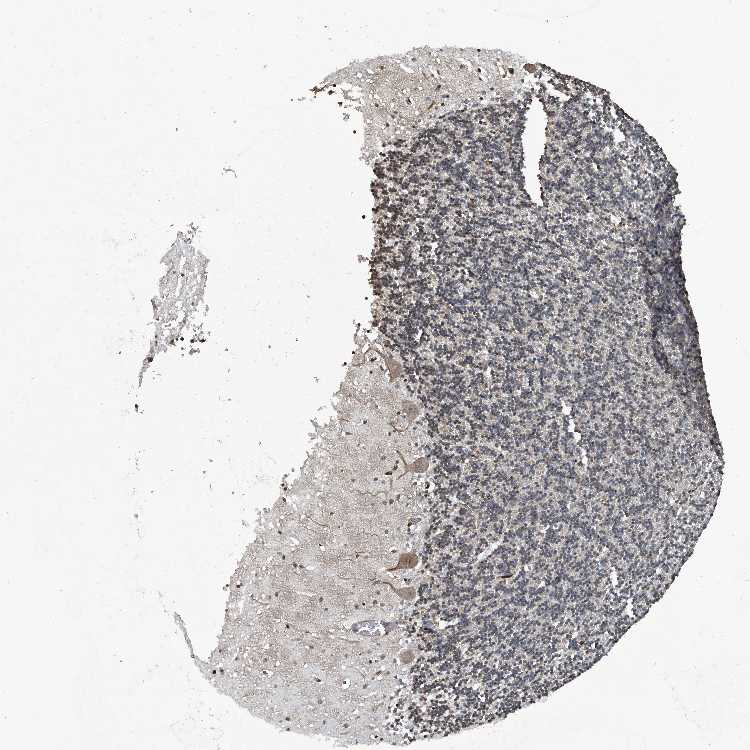

CEREBELLUM - Antibody stainingi

Antibody staining in the annotated cell types in the current human tissue is reported as not detected, low, medium, or high, based on conventional immunohistochemistry profiling in selected tissues. This score is based on the combination of the staining intensity and fraction of stained cells.

Each image is clickable and will lead to virtual microscopy that enables deeper exploration of all samples and also displays staining intensity scores, fraction scores and subcellular localization as well as patient and tissue information for each sample.

Antibody HPA029694Antibody HPA029695

Purkinje cells MediumLow

Cells in granular layer LowNot detected

Cells in molecular layer LowLow